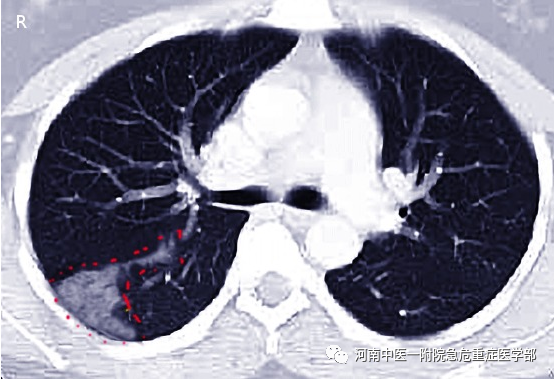

计算机断层扫描(CT)是最有可能结合临床表现诊断PI的影像学技术。与肺梗死相关的CT表现包括供血血管或“血管征”、中央透亮和半圆形。如果CT上出现中心透亮的血管征象而没有空气支气管征象,则检测PI的特异性为99%。

X线图像可能是诊断肺梗死的第一项检查。汉普顿隆起(肺周围楔形实变)、韦斯特马克征(影像学上血管纹理少或透亮增加)和弗莱舍征(肺动脉突出)是特异性表现,但缺乏足够的诊断敏感性。其他特征如肺不张或局灶性实变可能存在,但既不敏感也不特异。